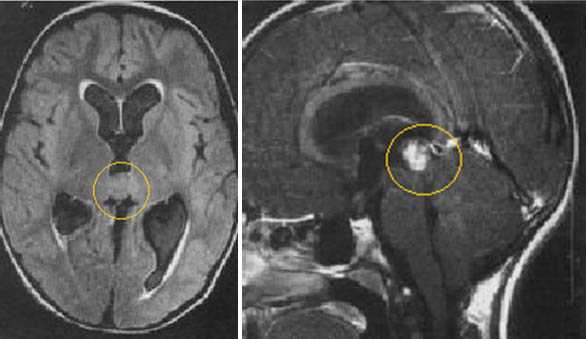

Герминома пинеальной области. На Т2 ВИ опухоль имеет слабо гиперинтенсивный сигнал по сравнению с тканью мозга, тогда как на Т1 опухоль практически изоинтенсивна с мозгом. Желудочковая система гидроцефально расширена. III желудочек деформирован. Четверохолмная пластинка оттеснена кзади.

Герминома пинеальной области. Опухоль имеет гетерогенное строение с множеством мелких и крупных кист. Вокруг опухоли определяется перифокальный отек.

Герминома пинеальной области с метастазированием в хиазмально-селлярную область.

Герминома подкорковых образований слева. Мультикистозного строения опухоль с признаками окклюзии отверстия Монро слева.